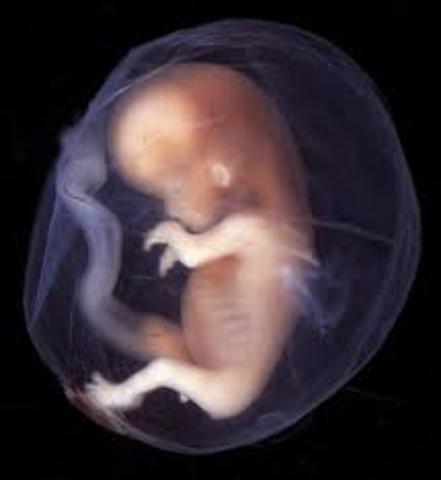

• Week 5

Week 5

The embryo now starts the process of shaping into a human. The placenta is developing and amniotic fluid begins to build up whcih will surround the fetus. The embryo is about 2-5mm.

• Week 6

Week 6

The embryo is beginning to form their main organs. The spinal cord begins to start closing, the brain begins to divide into its lobes, arms and legs are growing and the heart beat starts to play.